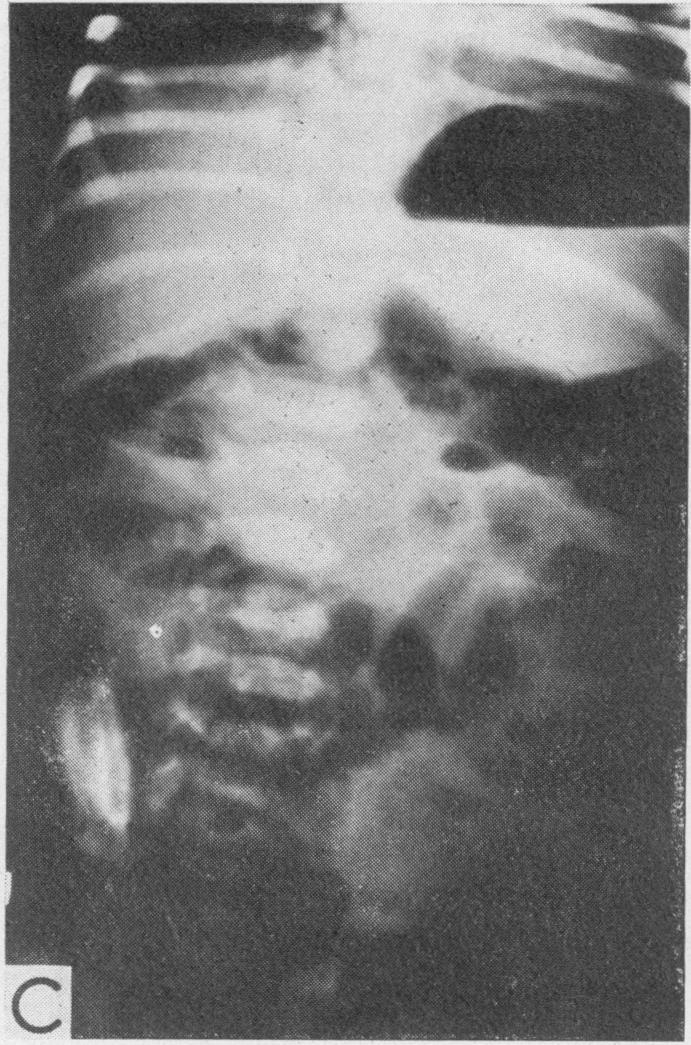

Pitfalls in the diagnosis of intestinal obstruction in the newborn.

Proc R Soc Med. 1971 Apr;64(4):374-7. doi: 10.1177/003591577106400417.